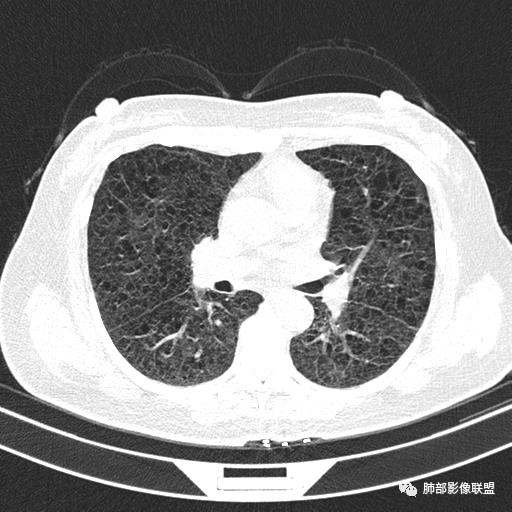

双肺弥漫囊腔,累及肋膈角,囊腔形态相对规则单一。

CT平扫示双肺弥漫分布大小不等囊状薄壁透光区,无内、中、外带分布差异,间质稍示增厚。拟LAM

中年女性育龄期妇女,咳嗽气喘,无吸烟史,有苯吸入史。影像:双肺弥漫均匀小囊腔,无明显分布优势,囊腔形态欠规则,壁薄,部分囊腔边缘血管征,伴双肺弥漫磨玻璃影,无结节,考虑lam,鉴别苯中毒肺损伤,囊腔多有分布优势,小叶中心分布为主,形态规整等

女,46,活动性气喘1年。苯吸入史半年。胸部CT:两肺弥漫囊腔,上至肺尖,下至肋膈角,形态类似小囊腔。考虑:LAM,鉴别LIP,BHD,PLCH等。

CT表现:双肺弥漫大小不等的薄壁囊腔,囊壁<2mm,外形规则,血管影多位于囊腔周围,囊腔之间肺组织正常,随着疾病进展到晚期,囊腔变大、增多,不可胜数,囊腔可融合成较大的囊,与肺气肿相似,形成间质性肺纤维化。部分病例可出现结节影。